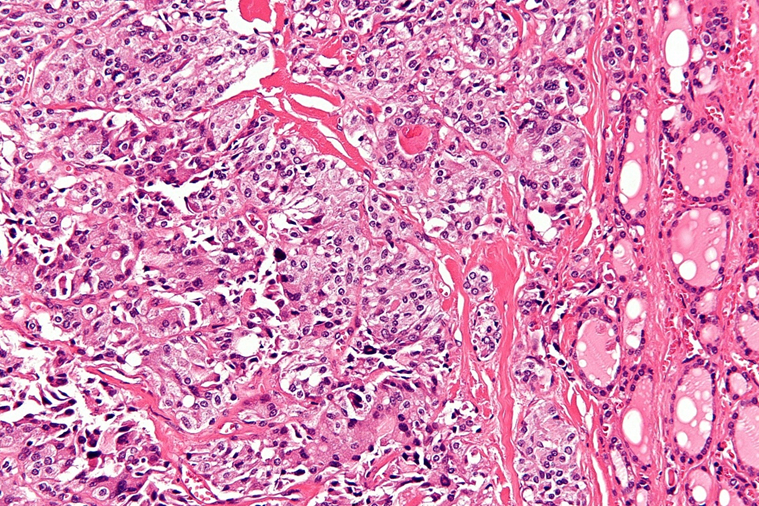

• 조직소견으로는 neuroendocrine tumor 답게 salt-and-pepper 패턴의 염색질이 관찰된다. 또한, 과도한 calcitonin 분비로 인해 아밀로이드로 침착된 섬유성 간질이 특징적으로 발견된다.

Medullary thyroid cancer, Wikipedia (Creative Commons License)